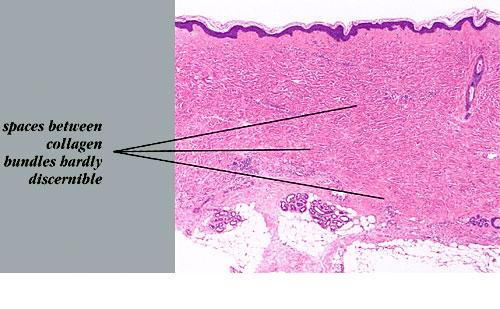

In the late sclerotic stage, as seen in the center of old lesions, the inflammatory infiltrate has disappeared almost completely, except in some areas of the subcutis. The epidermis is normal. The collagen bundles in the reticular dermis often appear thickened, closely packed, and hypocellular and stain more deeply eosinophilic than in normal skin (Fig. 10-13C, D). In the papillary dermis, where the collagen normally consists of loosely arranged fibers, the collagen may appear homogeneous.

The eccrine glands appear markedly atrophic, have few or no adipocytes surrounding them, and appear surrounded by newly formed collagen . In addition, instead of lying near the dermal-subcutaneous junction as in normal skin, they seem to lie higher in the dermis as a result of the replacement of most of the subcutaneous fat by newly formed collagen. This collagen consists of thick, pale, sclerotic, homogeneous, or hyalinized bundles with only few fibroblasts (hypocellular). Few blood vessels are seen within the sclerotic collagen; they often have a fibrotic wall and a narrowed lumen. Elastic stains show thick elastic